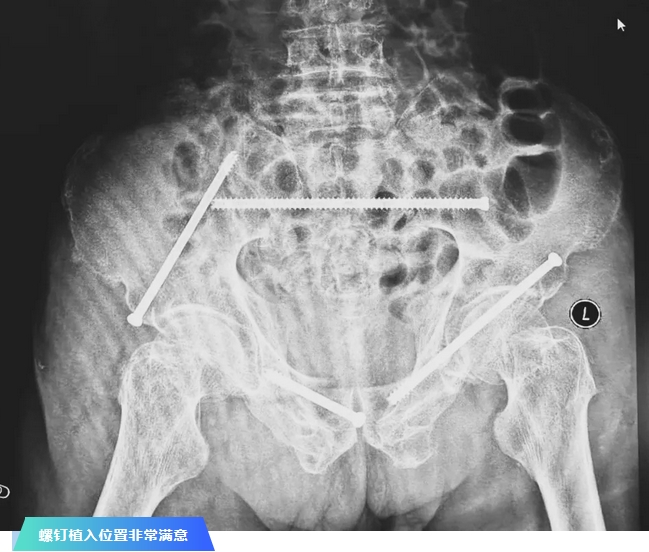

术后第二天,医生团队复查X片显示螺钉植入位置非常满意,骨折基本达到稳定复位,同时,复查的全血细胞计数中,血红蛋白指数为102g/L。术后第三天,在智能骨科病房护理团队及康复师的指导和护理下,王大爷可以坐立在床上。术后第四天,王大爷迎来了出院日,“得亏有了这么先进的医疗技术,让我还能下地行走,谢谢你们!”

在骨科手术机器人毫米级精度的引导下,这项原本高难度、高风险的手术变得更加精准高效。手术共计耗时1个半小时,术中出血不到20毫升,每枚螺钉置入位置的切口长度约1.5厘米,完美达到了预期。术后,王大爷安全返回病房。